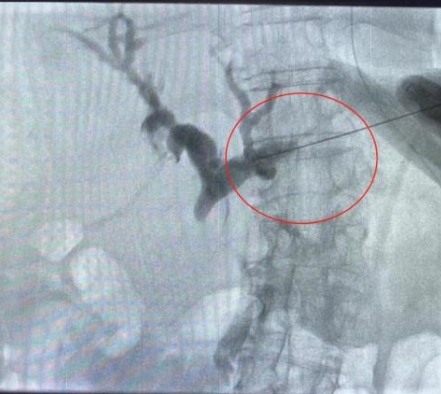

由于患者肝右葉占位巨大,完全遮擋右側(cè)穿刺路徑,左肝管為唯一穿刺路徑。介入科彭鵬醫(yī)生與重癥醫(yī)學(xué)科討論后,征得患者家屬同意后,擬行左側(cè)經(jīng)皮肝內(nèi)膽管穿刺引流術(shù)。術(shù)中一針便成功進(jìn)入膽道系統(tǒng),導(dǎo)絲引流管放置順利,造影顯示膽道系統(tǒng)顯影滿意,側(cè)孔位置可,引流順暢,37分鐘便結(jié)束了手術(shù),術(shù)后順利轉(zhuǎn)入普外科護(hù)理治療。這例手術(shù)的成功開展,刷新了該院介入團(tuán)隊(duì)高齡患者手術(shù)的新記錄!

經(jīng)皮肝內(nèi)膽管穿刺引流術(shù)是在醫(yī)學(xué)影像的引導(dǎo)下,利用穿刺針經(jīng)皮穿入肝內(nèi)膽管,注入對(duì)比劑,使肝內(nèi)外膽管迅速顯影后,置管引流以緩解梗阻癥狀。對(duì)于惡性梗阻性黃疸患者,通過該方式可降低血清膽紅素,有助于恢復(fù)肝腎功能,提高其生存質(zhì)量,延長(zhǎng)生存期,部分患者還可獲得進(jìn)一步治療的機(jī)會(huì)。對(duì)于良性梗阻性黃疸患者,除有利于迅速緩解黃疸和感染等癥狀外,還可為后續(xù)治療提供通道。